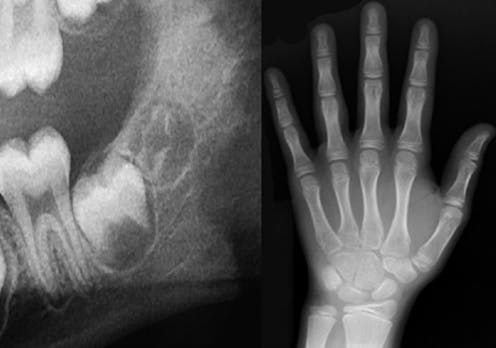

For children and teenagers, such an analysis can be carried out by examining X-rays. Growth and development are predictable processes, and milestones occur in a particular order. This is the reason that a tooth such as the first adult molar is also known as the “six-year molar,” because it generally erupts in everyone around age 6, give or take.

The analysis proceeds the same way whether we’re examining the X-rays of a living or deceased person. Essentially, we compare the stage of growth shown in the X-ray to existing growth charts from children and teenagers of known ages.

Sometimes, the estimated age range might include ages below and above 18. Take the development of the wisdom tooth, something we often look at when estimating age of older teenagers and young adults. But the development of this tooth is extremely variable, ranging from never developing at all to erupting anywhere from the mid-teens to early 20s. In such cases, how would a final decision of adult or minor status be made?